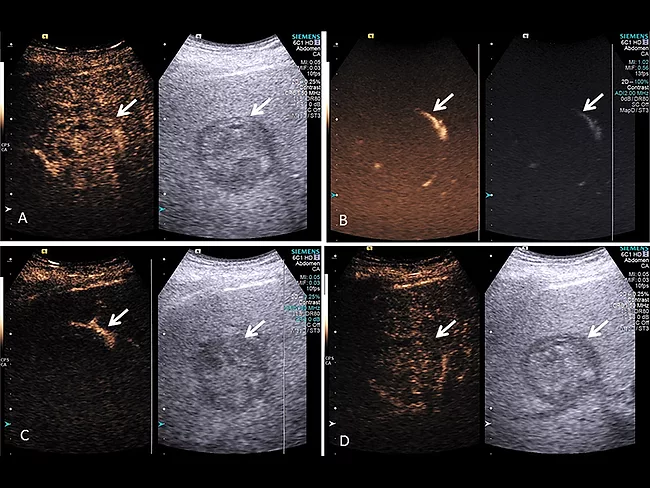

Microbubbles enhance response to TARE in liver cancer

Researchers at Thomas Jefferson University have found that using ultrasound to pop microbubbles already present in a contrast agent nearly doubled liver tumor response to transarterial radioembolization. The procedure raised no safety concerns and increased the likelihood of patients receiving a liver transplant.